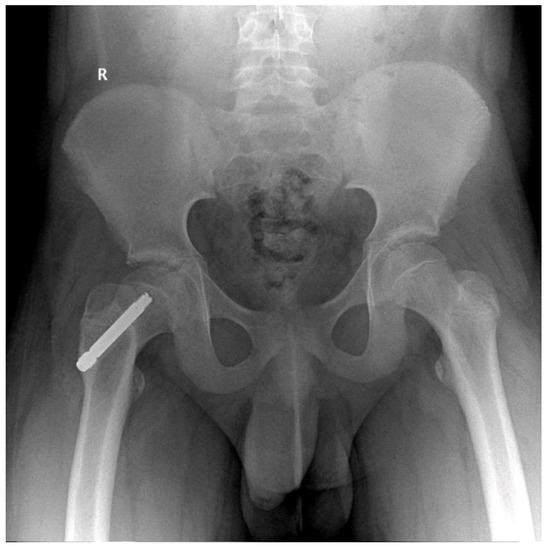

In two cases, at 16 months postoperatively we observed screw failure (entire screw slipped) Figure 2, most likely due to accidental crossings with the drill through the growth cartilage, and of an insufficient number of threads passed through the physis (three). No patient having at least four threads passed over the physis presented with slippage or no telescoping of the screw.

Figure 2.

Male patient, 9 years old, slipped screw at 16 months follow-up.